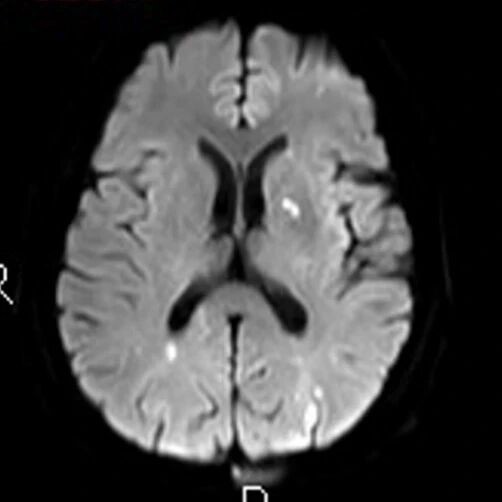

“双梗并发,嗜酸为祸”——特发性嗜酸粒细胞增多症并发心肌梗死与脑梗死一例